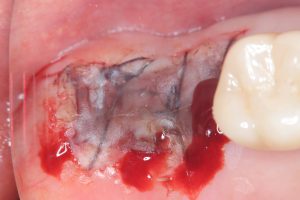

リムーブに、埋入、移植ボリュームアップに根面被覆👍

供給側、S.Bだけ、このやり方が1番ダメージ少ない

知らない方多い!

S.Bは万能です!